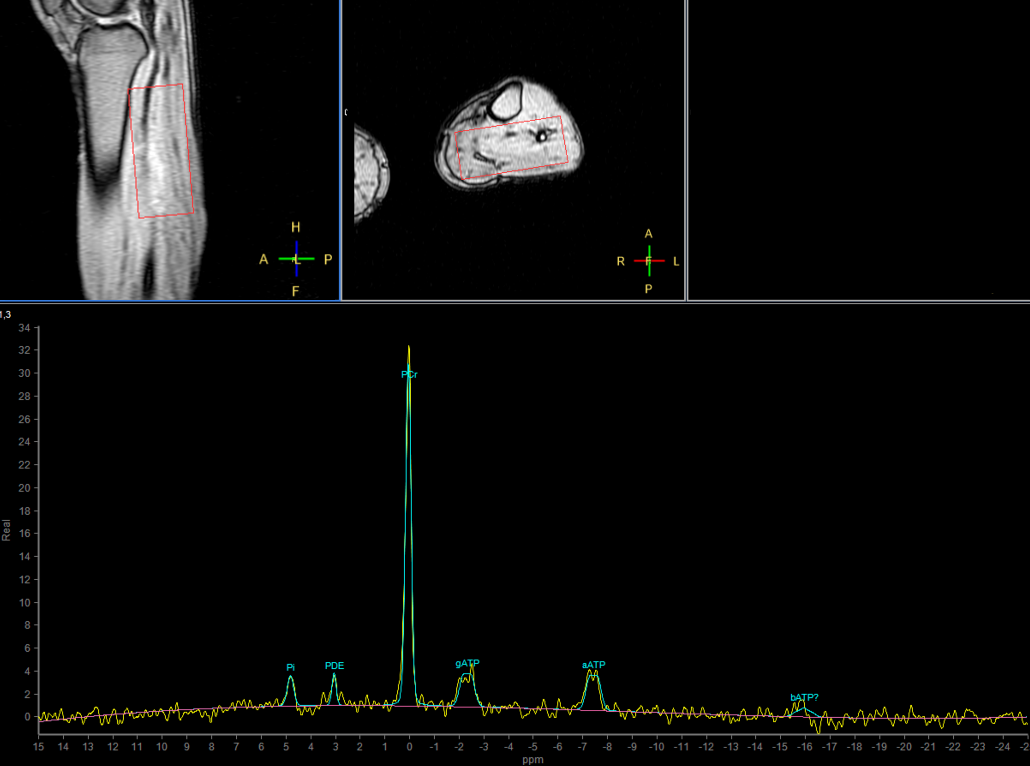

31P Phase Acquired (5 sec/acq, 50 dynamics)

31P Phase Acquired (Rest - Stress - Recovery)

31P Phase Acquired (Rest)

31P Phase Acquired (Stress)

31P Phase Acquired (Recovery)